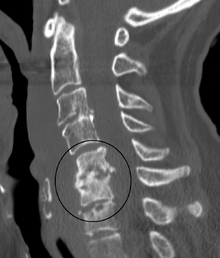

Diagnosis is usually apparent on MRI although plain X-rays and CT examinations can be suggestive. The MRI will reveal air changes in the disc and possibly even external involvement involving the bone or epidural regions. A biopsy may be performed and helps with diagnosis in some cases but often an organism is not obtained. C-reactive protein levels and ESR levels will be elevated and are useful for treatment. Often, the white blood cell count will be normal and the patient will be afebrile.